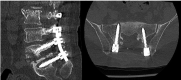

Spondylodiscitis is an uncommon but serious complication after spine surgeries, and its main etiologic agent is Staphylococcus aureus . Fungal infections are rare and mostly caused by Candida albicans . We report the clinical case of a 69-year-old male patient who underwent a L2-S1 arthrodesis for degenerative scoliosis correction. He presented an infection 2.5 months after the procedure, a spondylodiscitis at L5-S1 levels, caused by Candida parapsilosis . The treatment consisted of surgical material removal, tricortical iliac graft placement in an anterior approach (L5-S1), lumbopelvic fixation (from T10 to the pelvis) in a posterior approach, and drug treatment with anidulafungin and fluconazole. This last medication was administered for 12 months, with good clinical outcomes.